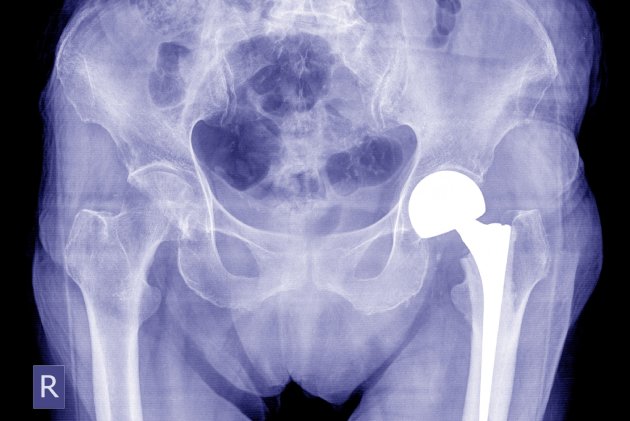

Las Prótesis de cadera en Monterrey, N.L. ofrecen una solución efectiva para problemas de cadera, consulte a nuestros especialistas en Traumatología y Ortopedia para obtener más información.

Nuestro centro médico en Monterrey, N.L. cuenta con equipos y técnicas de última generación para realizar procedimientos de Prótesis de cadera con los más altos estándares de calidad en Traumatología y Ortopedia.